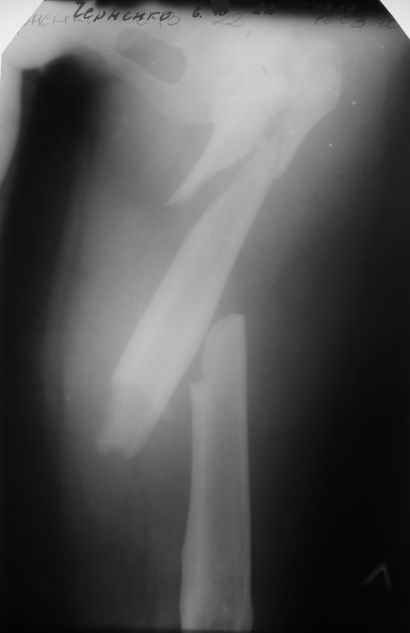

Пациентка 23 лет, доставлена в клинику с Диагнозом: Закрытый сегментарный оскольчатый перелом левой бедренной кости в верхней и средней трети. Травма в результате ДТП 10.03.2006г. Из анамнеза у пациентки диспластический левосторонний коксартроз, S-образный сколиоз 2ст. В 1999г в Кургане выполнялась остеотомия бедра в нижней трети и коррекция укорочения конечности на 3 см (рентгенограммы бедра и таза до травмы в приложении). До получения травмы пациентка ходила без боли с полной нагрузкой на левую ногу. Учитывая дисплазию левого ТБС, пациентке, вероятно, предстоит операция тотального эндопротезирования лев ТБС, что требует анатомичного восстановления проксимального отдела бедра.

Рассматриваются следующие вариант остеосинтеза: 1) Экстракортикальный остеосинтез проксимального и дистального перелома пластиной с угловой стабильностью типа LISS( г Рыбинск);

2) Ретроградный интрамедуллярный блокированный остеосинтез дистального перелома и накостный синтез проксимального пластиной с угловой стабильностью;

3) Остеосинтез бедра в аппарате внешней фиксации с фиксацией таза и возможной открытой адаптацией фрагментов.